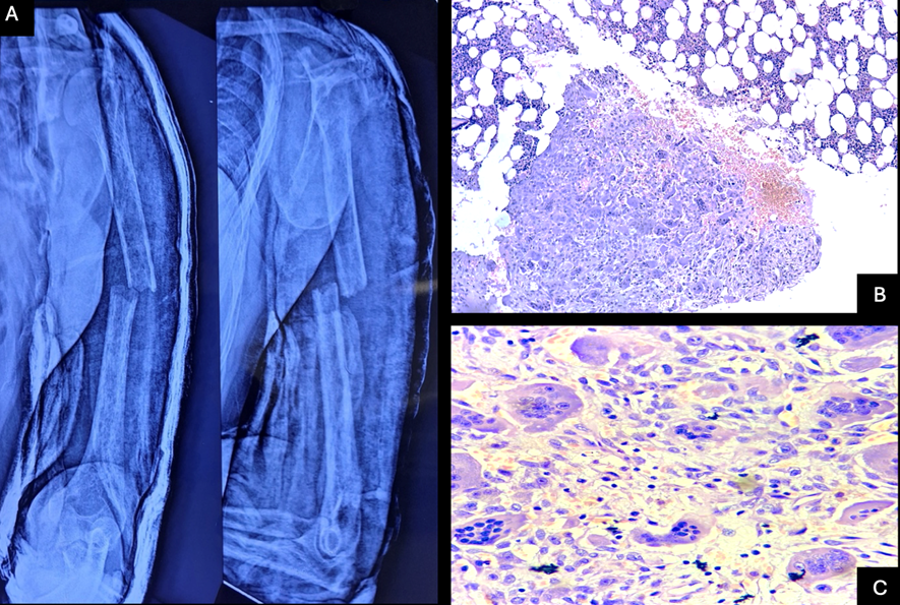

unremarkable hematopoietic elements [Figure 2].

|

| Figure

2: A - Pathological fracture of the left

humerus in Case 2. B- Low power view

photomicrograph intervening areas of

trabeculae showing trilineage

haematopoiesis and areas of haemorrhage.

Haematoxylin and eosin stain (H & E,

10X). C - High power view photomicrograph

showing groups and clusters of

multinucleated osteoclastic giant cells

(arrow) along with cells having oval to

spindle bland nuclei with indistinct cells

borders and eosinophilic cytoplasm.

Histiocytes and hemosiderin laden

macrophages also seen. Haematoxylin and

eosin stain (H & E, 40X) |